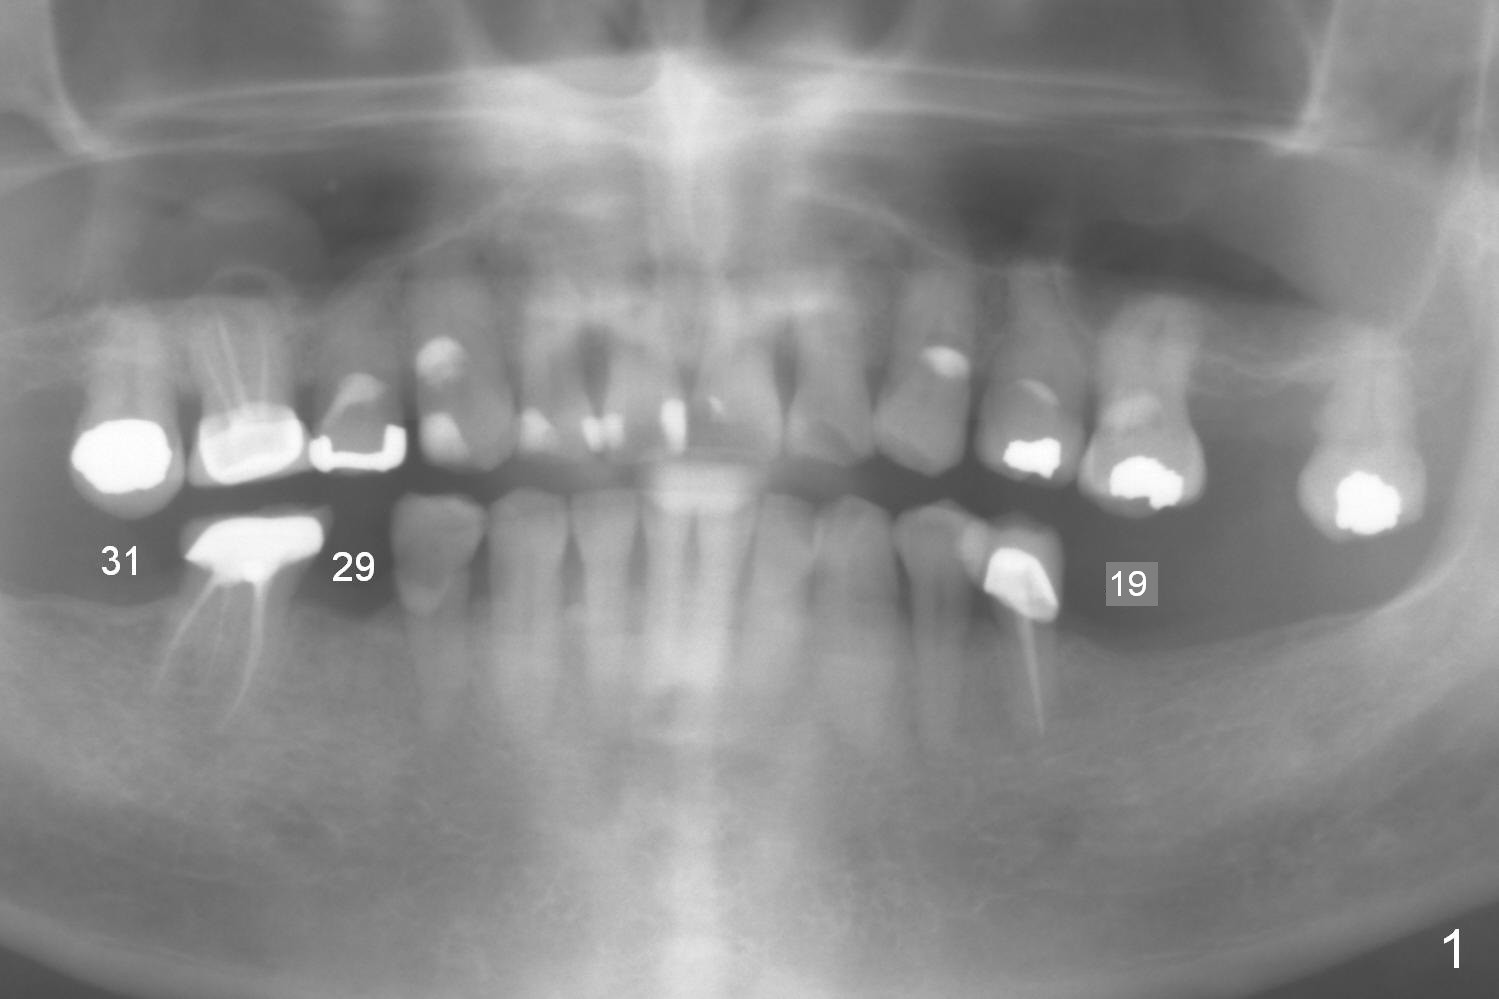

Early Loading for Intrusion A 66-year-old man has 3 missing teeth (Fig.1: #19,29,31) with supraerupted opposing teeth. Because of sufficient bone height (Fig.2: 13 mm (preferably 15 mm) fixture) and special fin pattern of IBS implant (stability), early loading (2 months, as opposed to 3 months in a previous case) is possible with a provisional to be placed at #19 to intrude the tooth #14. Start with Magic Split for access, bone density test and bone expansion if necessary. Place the implant deep. If primary stability is high, fabricate an immediate provisional with occlusal clearance. Reline the provisional for occlusal contact 2 months postop. Reline the provisional again so that it is able to intrude the tooth #14. Return to